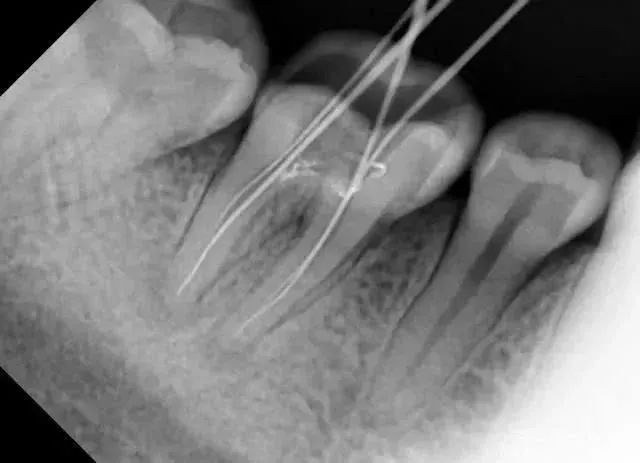

拍一次小视野CBCT

=50微西弗

=50张小牙片

=500根香蕉

等于坐飞机12.5小时

拍一次小视野CBCT=吃500根香蕉